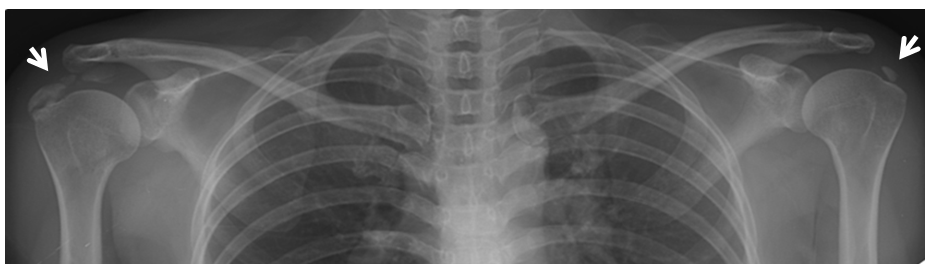

X-ray: 석회화된 부위를 확인할 수 있으며, 이는 석회성 건염의 가장 명확한 징후 중 하나입니다.